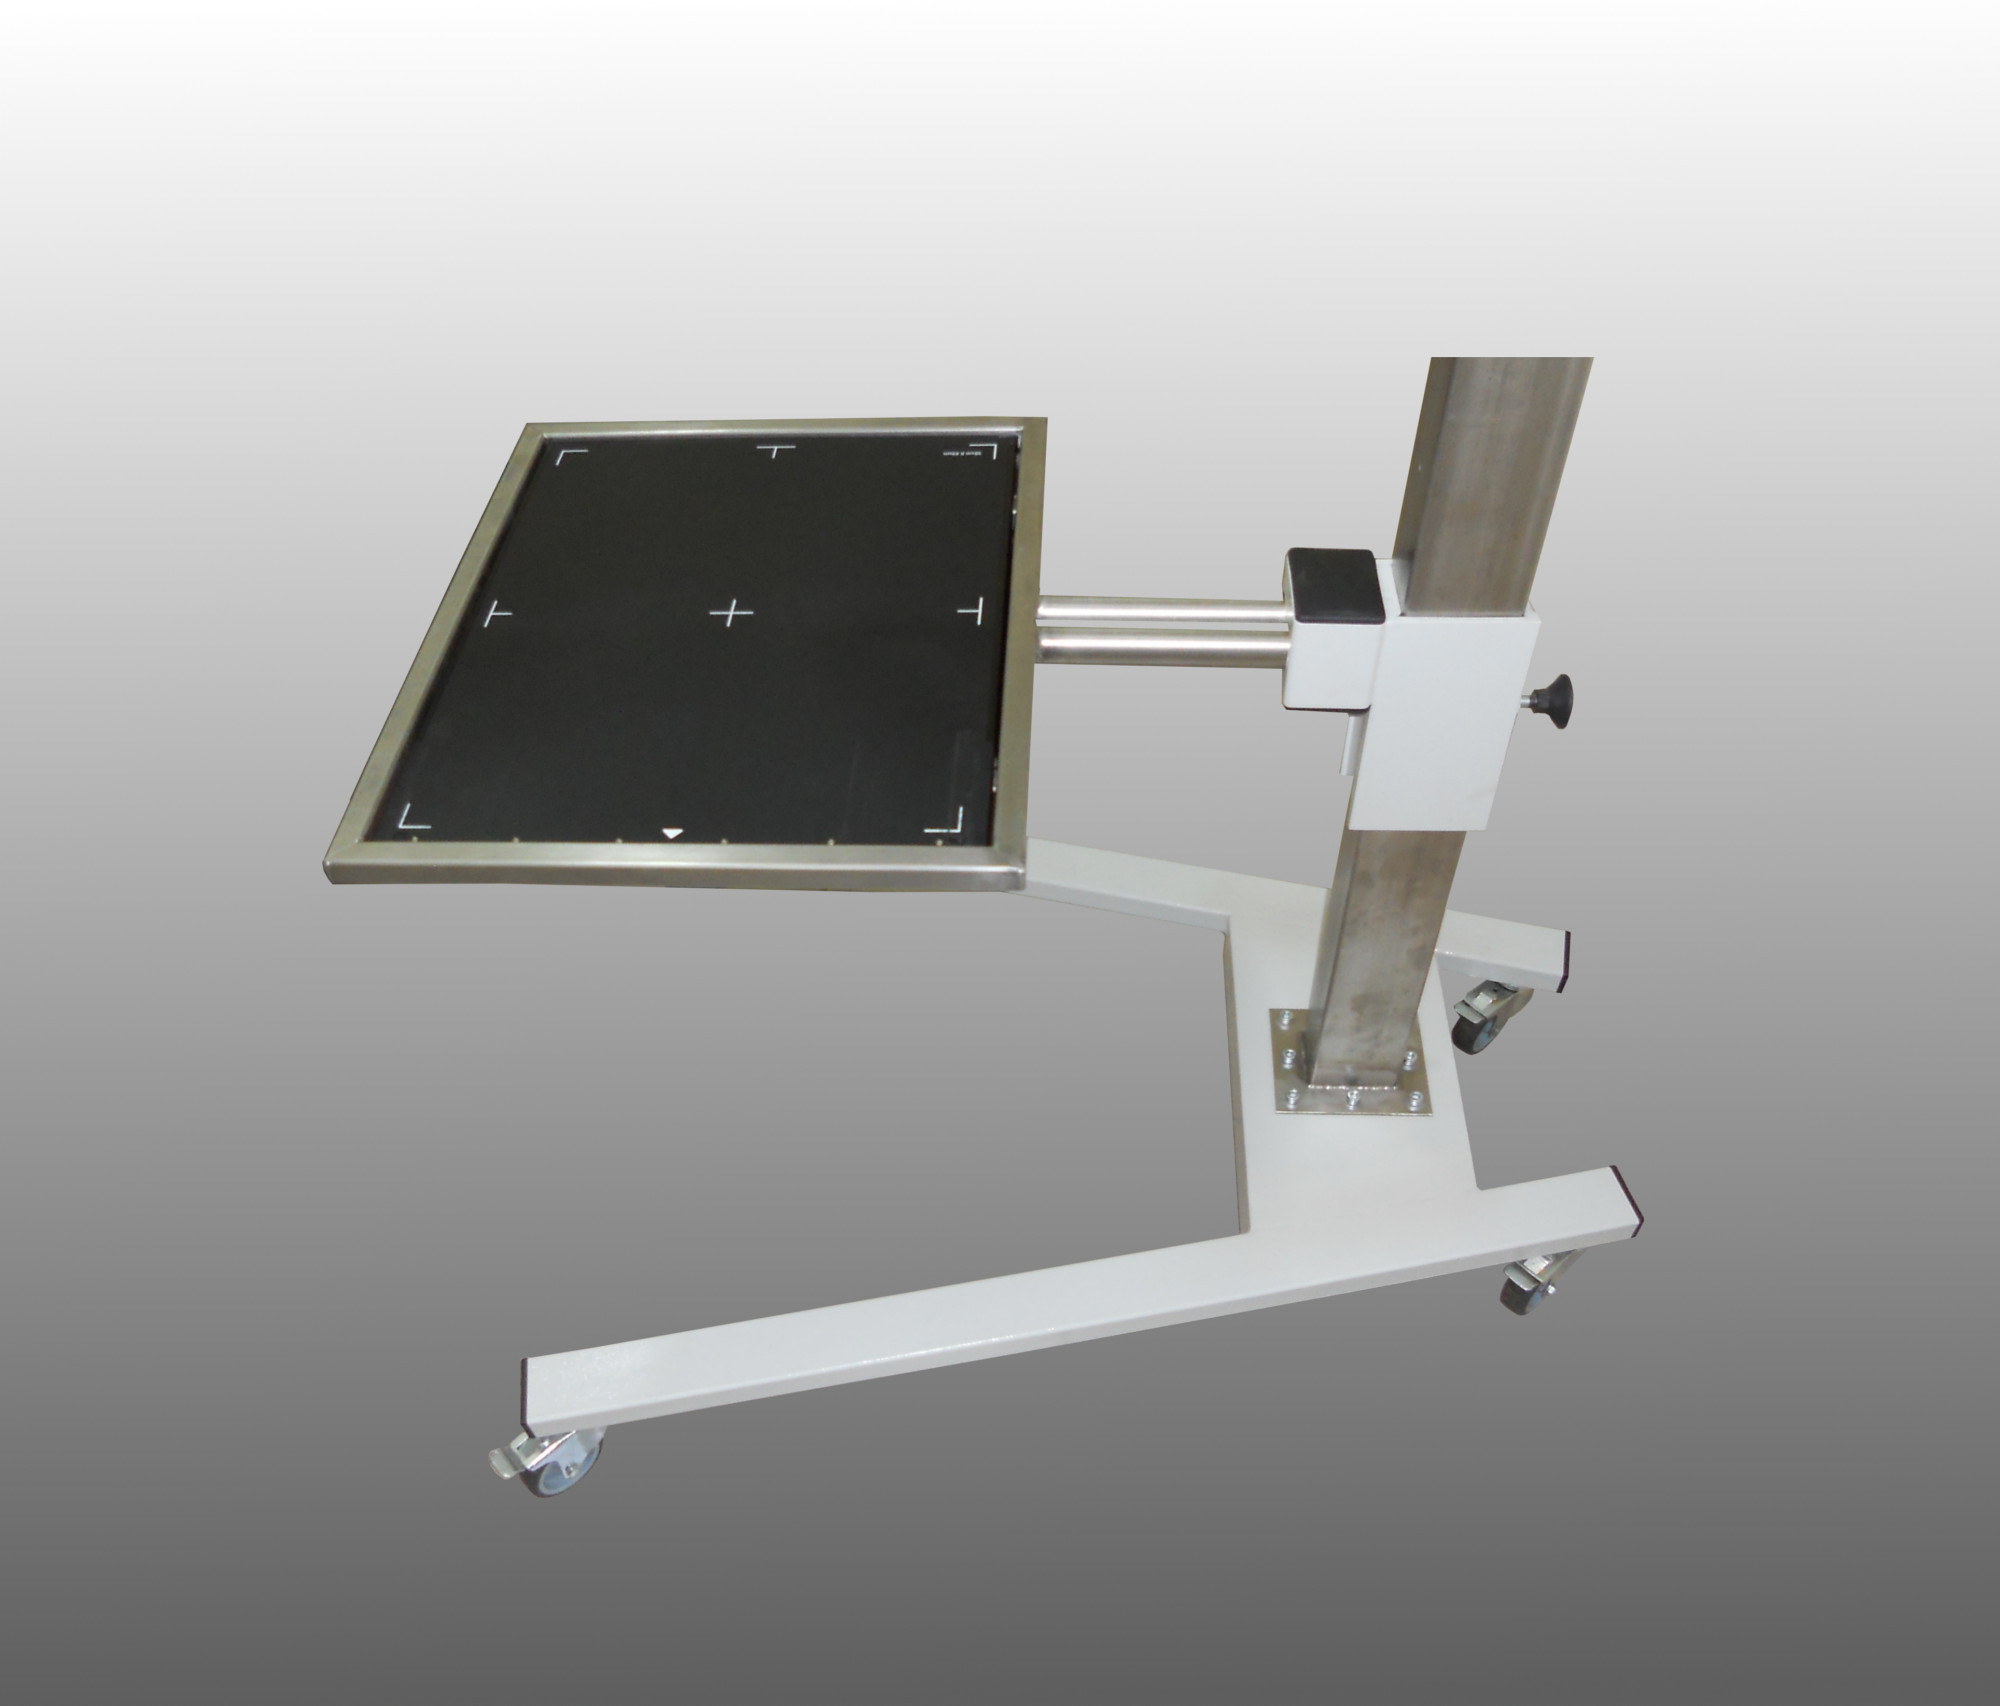

Организация рабочего пространства: стенды для рентгеновских снимков